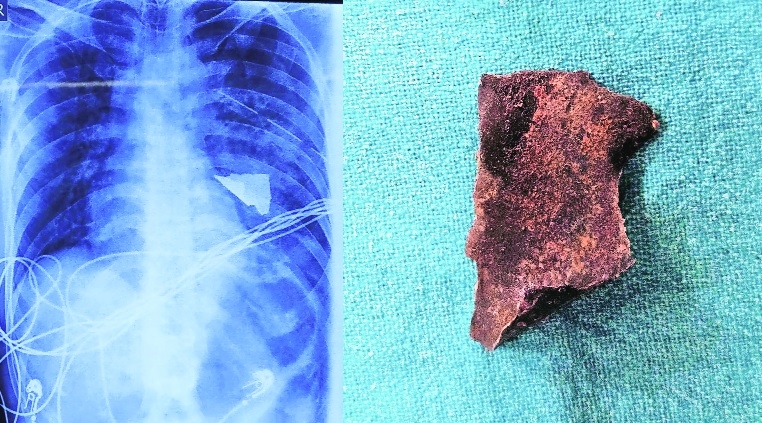

The metalic fragment is visible in X-ray. (Right) It is kept on the table after removing it from lung.

In a rare and challenging case, a young man employed in heavy metal smelting, who was a sculptor, was successfully operated on after a high-velocity, triangular-shaped metallic fragment penetrated his chest wall and lodged into his left lung. The team of doctors at Super Speciality Hospital removed the metal from the lung. The patient presented in a critical condition with haemopneumothorax, active bleeding from the entry wound, and signs of shock. Complicating the case further, the patient was a chronic tobacco chewer with severely restricted mouth opening, making airway management and intubation extremely difficult. Despite these challenges, the anaesthesia team successfully performed lung isolation with a bronchial blocker. As the left lung had to be deflated for a clear and easy approach for the removal of the metallic piece, air entry was blocked in the affected lung, which was deflated and isolated. The 5×3 cm piece of metal managed to pierce the chest wall and get lodged deep inside the left lung in the upper lobe. Miraculously it missed the heart and all the major vessels in the chest, although a small piece of the lung had to be removed, as it was shredded beyond repair by the shrapnel.